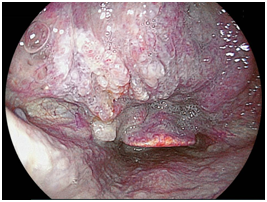

We detected 11 cases of superficial squamous cell carcinoma of the base of the tongue between April 2012 and March 2016. All the patients were complicated with current (n=3) or previous (n=8) esophageal squamous cell carcinoma. The patient characteristics are shown in Table 1. The mean age of the patients was 63.7years (range, 49-73years), and all patients were male. Four cases were diagnosed using trans-nasal endoscopy with the FICE system, seven cases were diagnosed using trans-nasal endoscopy with the LASERIO system. The average time to complete a thorough examination for one patient was approximately from 1 to 2minutes, regardless of the presence of abnormal findings. Biopsy specimen were obtained in all patients, and diagnosed as squamous cell carcinoma pathologically. Table 2 shows the treatment results. Five lesions were flat type (Figure 4A), four were elevated (Figure 4B), and two were depressed (Figure 4C). Regarding the tumor size, eight were T1, three were T2. No lymph node metastasis was detected in any case. Six cases were treated by endoscopic laryngo-pharygeal surgery,15 and 3 cases were treated by chemo-radiotherapy. One case was followed because of esophageal cancer. One case was treated by trans-oral robotic surgery at another hospital. For the seven resected specimens, the median tumor thickness was 800μm (range, 250-3000μm), and the median tumor diameter was 11mm (range, 10-25mm). Histologically, two of these lesions were squamous cell carcinoma in situ, five showed microinvasion of the subepithelial tissue. During a median follow-up period of 26months (range,11-56months), 1 patient, which patient’s tumor thickness was 3000μm, developed lymph node metastasis, which was treated by neck lymphadenectomy and chemo-radiotherapy. Three of the 11 patients cases were died of another disease, and 8 were alive as drafting this manuscript.

Figure 4A Flat type

Macroscopic types of superficial squamous cell carcinoma of the base of the tongue.